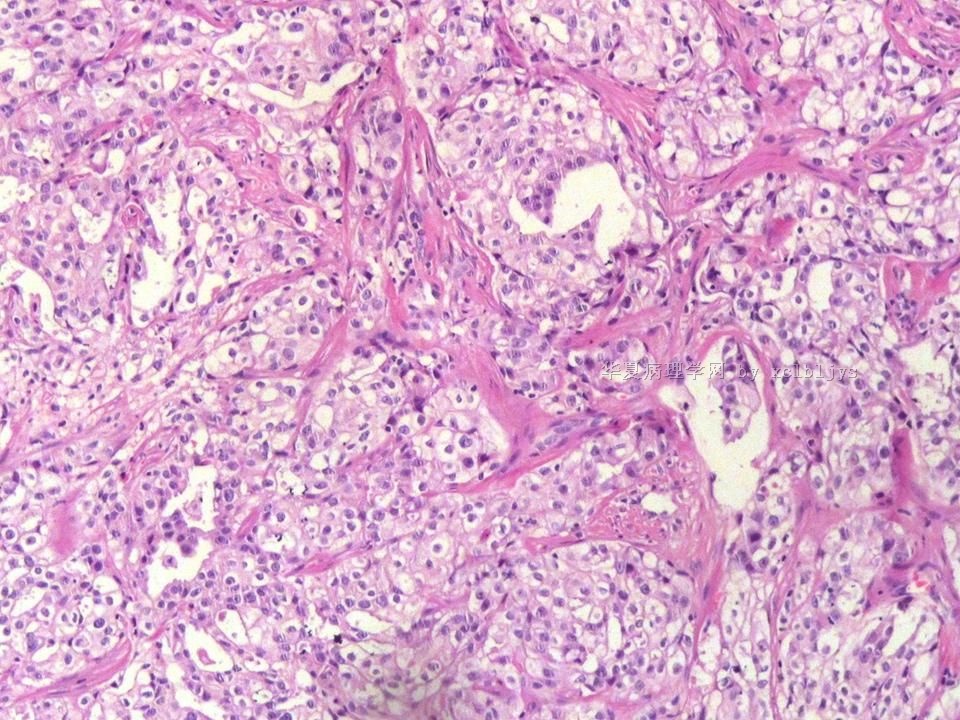

姓    名: ××× 性别:  男 年龄:  56

左锁骨上肿块三月余,手术切除。

蚕豆大肿块,包膜较完整,切面灰红色,质软。

• 左锁骨上肿块(IHC)图1

图1

转移癌

首先考虑甲状腺或肺来源

转移性腺癌。清查胃、肺等处有无原发灶。

转移性腺癌,请查消化道

免疫组化结果:TTF-1(+),CK7(+),CK20(-),TG(-)。临床近一步检查,肺未见肿块,左甲状腺发现肿块,目前仍未处理。

从形态结构看,有腺泡也有乳头结构,倾向转移性肺腺癌。